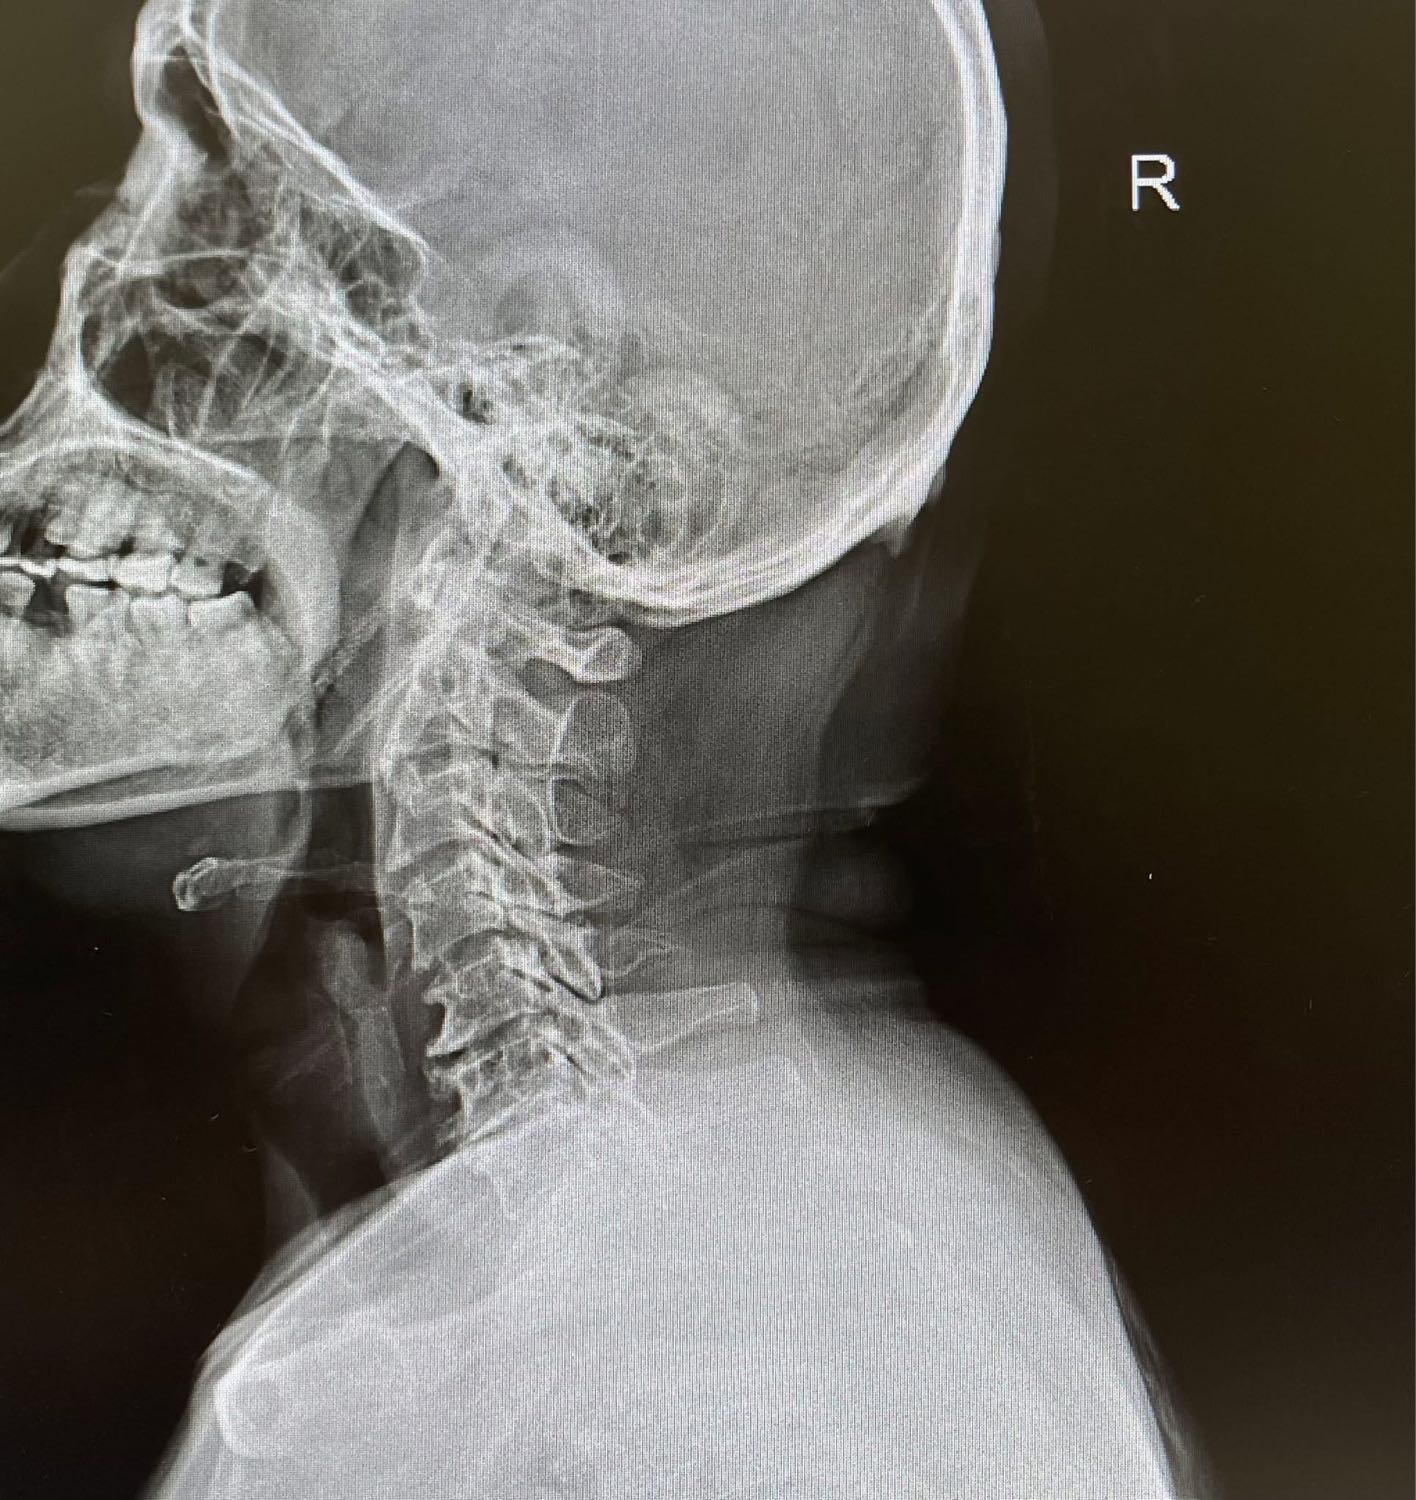

สรุปเคสนี้ไม่ใช่ไมเกรนครับ แต่เป็น "คอเสื่อมจากการก้มทำงาน" พอรักษาที่คอ อาการปวดหัวที่เบ้าตาก็หายไปเองโดยไม่ต้องกินยาไมเกรนอีกเลย

เส้นประสาทที่รับความรู้สึกจาก "คอส่วนบน" (C1-C3) มันส่งสัญญาณเข้าไปที่ก้านสมอง ซึ่งดันไปเป็นจุดเดียวกับที่รับสัญญาณจาก "ใบหน้าและศีรษะ" (Trigeminal nerve)

พอกระดูกคอเสื่อม หรือกล้ามเนื้อคอเกร็งมากๆ มันส่งสัญญาณเจ็บปวดไปที่ก้านสมอง... สมองเกิดความสับสนครับ นึกว่าความเจ็บนั้นมาจาก "หัว" หรือ "ตา" ก็เลยแปลผลออกมาเป็นอาการปวดหัวตุบๆ นั่นเอง